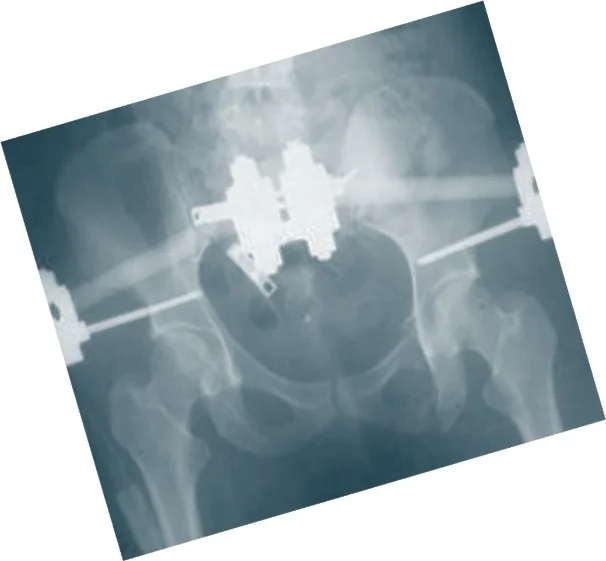

Operative Treatment Options

- External fixation

- Temporary Clamp

-

Internal fixation

- Screws & Plates

Combinations